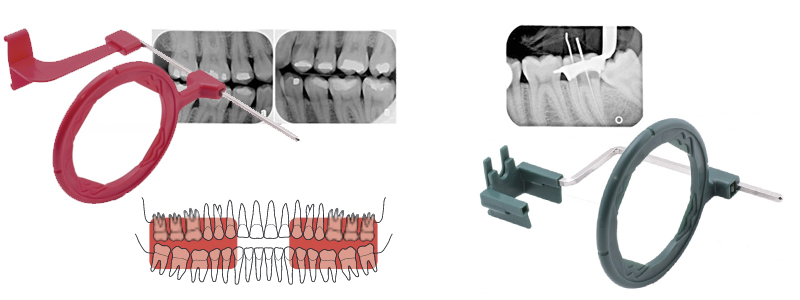

De plus, à l’intérieur de chaque variété de couleurs, nous pouvons trouver différents blocs d’occlusion en fonction de la taille du film intrabuccal. De plus, si vous voulez réaliser une fotographie verticale ou horizontale, il existe deux types différents de positionneurs XCP. Vous pouvez voir la différence entre ces deux types sur l’image qui suit :

Il existe deux configurations qui permettent la prise de vue de quatre hémiarcades, en inversant simplemnt la position de la plaque :

- Image nº1: Assemblage du XCP pour réaliser la radiographie maxilaire superieur droite (Premier Quadrant), il suffit de le retourner pour la mâchoire gauche (Troisième Quadrant)

- Image nº2: Assemblage du XCP pour réaliser la radiographie maxilaire superieur gauche (Second Quadrant), il suffit de le retourner pour la mâchoire droite (Quatrième Quadrant)